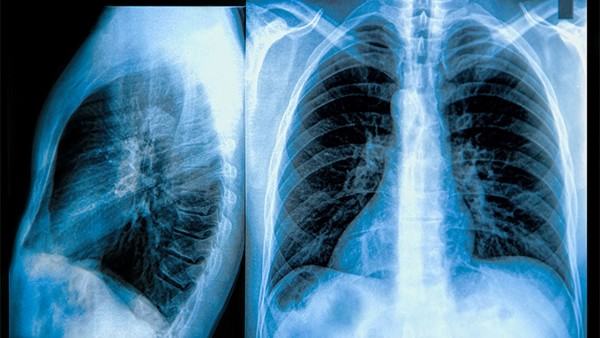

胸膜炎患者需要做哪些检查

胸膜炎(Pleuritis)是指胸膜的炎症,胸膜是包裹在肺表面和胸腔内壁的一层薄膜。胸膜炎可以由多种原因引起,包括感染、创伤、肿瘤以及自身免疫性疾病等。确诊和了解胸膜炎的原因至关重要,因此,这些患者需要进行一系列的检查。 1. 病史和体格检查 在进行任何医学检查之前,医生会首先详细询问患者的病史,包括症状的出现时间、性质(如疼痛的部位、性质是否刺痛、压痛等)、伴随症状(如咳嗽、发热、呼吸急促等)以及潜在的病因(如既往的肺部疾病、近期是否有感染等)。体格检查中,医生会听取患者的肺部声音,以发现是否有呼吸音减弱或异常的声音,这可能是胸水积聚的迹象。 2. 影像学检查 X线胸片 X线胸片是胸膜炎患者常规检查的第一步。此检查可以帮助医生观察到胸腔内是否有液体积聚(胸水)、肺不张或炎症等。胸水可反映出胸膜炎的严重程度和病因。 CT扫描 如果X线结果不明确,医生可能会建议进行CT扫描。胸部CT扫描能提供更清晰、更详细的图像,帮助识别胸膜和肺部的异常,评估胸水的特征以及寻找潜在病因,如肿瘤或感染灶。 3. 超声检查 胸部超声检查是一种无创的检测方法,可以有效评估胸水的存在、性质以及位置。超声能够帮助医生决定是否进行胸腔穿刺,以提取胸水进行进一步分析。 4. 胸腔穿刺 通过胸腔穿刺(胸膜穿刺),医生可以抽取胸腔内的液体以进行分析。胸水的性质(如清澈、浑浊、血性等)和细胞学、化验结果(如细菌培养、肿瘤标志物等)能够帮助判断胸膜炎的病因,从而指导治疗方案。 5. 实验室检查 血液检查也是帮助诊断胸膜炎的重要手段,包括: 全血细胞计数:可以发现白细胞增多,提示感染或炎症。 C反应蛋白(CRP):炎症指标,通常在急性炎症状态下升高。 血培养:如果怀疑细菌感染,血培养可以帮助识别病原体。 如果怀疑为结核性或其他特定感染性胸膜炎,可能还需要进行特定的检查(如结核菌素试验或胸水中抗酸杆菌的检测)。 6. 特殊检查 在某些情况下,若怀疑有肿瘤、结核或其他特定疾病,可能需要进行更进一步的检查,比如支气管镜检查、组织活检等。 结论 胸膜炎是一种可能由多种原因引起的疾病,准确的诊断需要多种检查手段的综合运用。通过详细的病史、体格检查以及影像学、实验室和特殊检查,医生能够找出引起胸膜炎的根本原因,并制定合理的治疗方案。胸膜炎的早期识别和及时治疗对于患者的恢复至关重要,这不仅能减轻症状,还能防止并发症的发生。